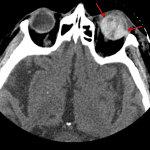

- Traumatic left retinal detachment with intraocular hemorrhage

- Traumatic retinal detachment

Traumatic left retinal detachment with intraocular hemorrhage. Globes are intact. No retrobulbar hemorrhage or proptosis. No acute facial fracture.